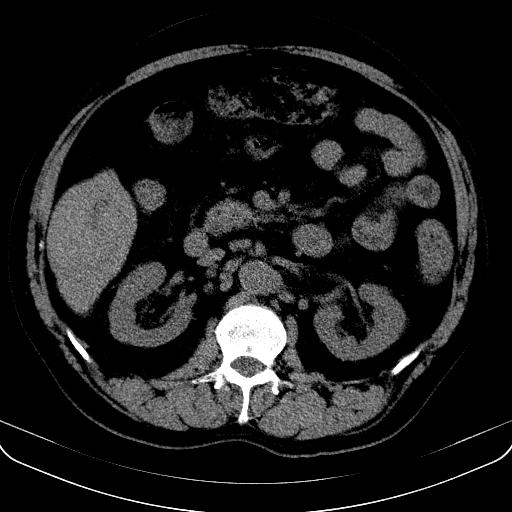

以下是引用jia119在2008-3-5 13:31:00的发言:[br]肝内多发片状低密度影,密度不均,我还是考虑肝ca可能,另肝内小囊肿,胆囊增大。

以下是引用形影不离在2008-3-5 12:18:00的发言:[br]肝硬化伴门脉高压征,肝内占位待排,增强再说.

以下是引用随光逐影在2008-3-5 21:11:00的发言:[br]肝硬化伴门脉高压(食管下段静脉曲张),肝癌不排除。建议:行ct增强扫描检查。

以下是引用同在2008-3-5 13:56:00的发言:[br]考虑肝癌可能性大,胆囊增大.